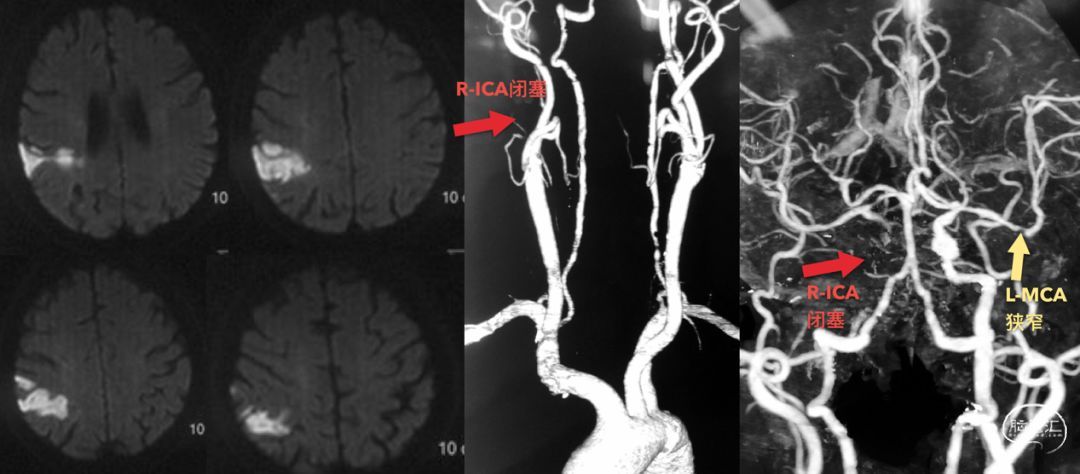

患者:男性,69岁,因言语不清、记忆力显著下降20天入院,患者20天前突然发病,当地MRI证实右侧半球皮层梗塞,CTA提示右侧ICA闭塞。

患者还在当地进行了造影,提示右侧ICA闭塞,眼动脉代偿,返流到ICA的岩骨段;另有前交通代偿,但似乎代偿比较差。

入院后,我们补充了几项检查,包括灌注、高分辨核磁,并复查造影。灌注提示:右侧半球CBF降低、TTP和MTT延长。但由于左侧MCA狭窄,所以并不非常显著。

术后情况一直很好,直到1月前,患者反复多次出现左侧肢体力弱,MRI显示明确的右侧半球多发梗塞灶。判断机制应该是低灌注和栓塞都有的混合机制。

当地医院很快完成了造影检查,发现右侧ICA闭塞,通过前交通动脉和眼动脉代偿。

当地医院灌注检查提示:右侧半球灌注不足。